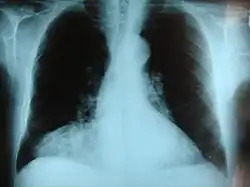

Morgagni hernia seen on a chest radiograph.

Congenital diaphragmatic hernia (CDH) is a birth defect of the diaphragm. The most common type of CDH is a Bochdalek hernia; other types include Morgagni hernia, diaphragm eventration and central tendon defects of the diaphragm. Malformation of the diaphragm allows the abdominal organs to push into the chest cavity, hindering proper lung formation.